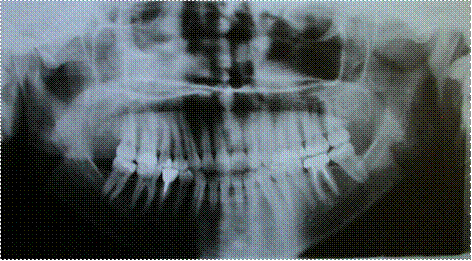

Рентгенологические исследования ортопантомограмм 18 пациентов показали, что резцы имели сформированный корень. Наличие сформированного корня у резцов при вертикальной резцовой дизокклюзии, величины вертикальной щели между ними в среднем 6 мм и зубоальвеолярного укорочения в области резцов на 4,51-5,21мм - подтверждают необходимость комбинированного лечения этой аномалии.

Рис. 3.2.7. Фото отртопантомограммы больного «А», 29 лет, основная группа, до лечения.

Рентгенологические исследования ортопантомограмм 18 пациентов показали, что резцы имели сформированный корень. Наличие сформированного корня у резцов при вертикальной резцовой дизокклюзии, величины вертикальной щели между ними в среднем 6 мм и зубоальвеолярного укорочения в области резцов на 4,51-5,21 мм, подтверждают необходимость комбинированного лечения этой аномалии.